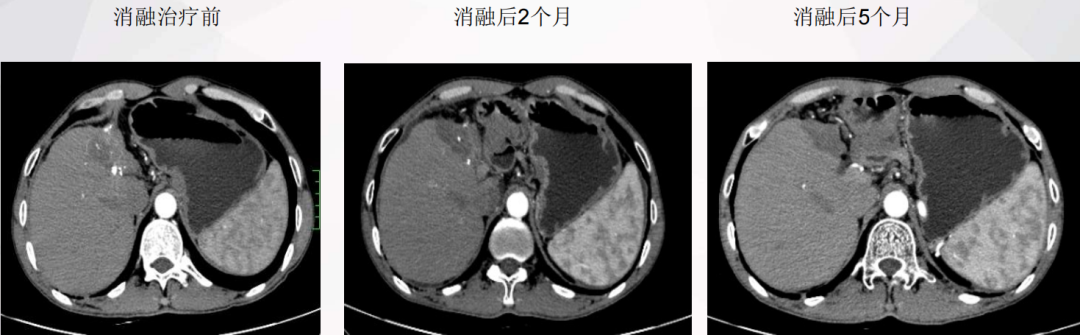

消融后的变化:

↓↓↓

目前,患者已经接受综合治疗超过 12 个月,各项临床肿瘤评价指标正常,生活质量良好,显示出良好的临床治疗效果。 这个案例再次证明了晚期肝癌综合治疗的重要性和可靠性。